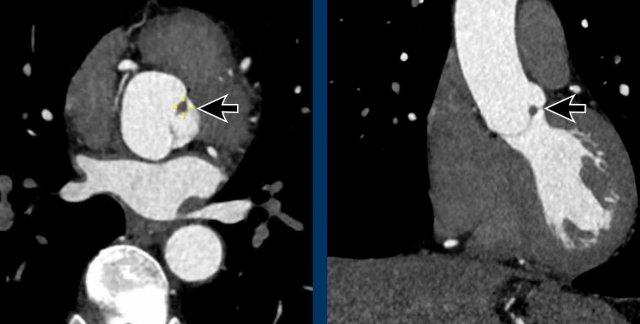

U xơ đàn hồi nhú của van động mạch chủ

CT ngực không đồng bộ ECG không hiển thị rõ các van tim, tuy nhiên đôi khi vẫn có thể phát hiện các bất thường.

Như đã đề cập ở trên, các phát hiện tình cờ chính tại van sẽ là vôi hóa van động mạch chủ và van hai lá.

Một phát hiện hiếm gặp là u xơ đàn hồi nhú (mũi tên), đây là khối u nguyên phát thường gặp nhất liên quan đến các van tim, chủ yếu ở van động mạch chủ hoặc van hai lá.

Hình ảnh CT điển hình của u xơ đàn hồi nhú là một khối nhỏ không đều, có cuống, liên quan đến van tim.

Thường gặp nhất là phát hiện tình cờ không có triệu chứng, mặc dù u xơ đàn hồi nhú có thể gây biến chứng tắc mạch hệ thống.